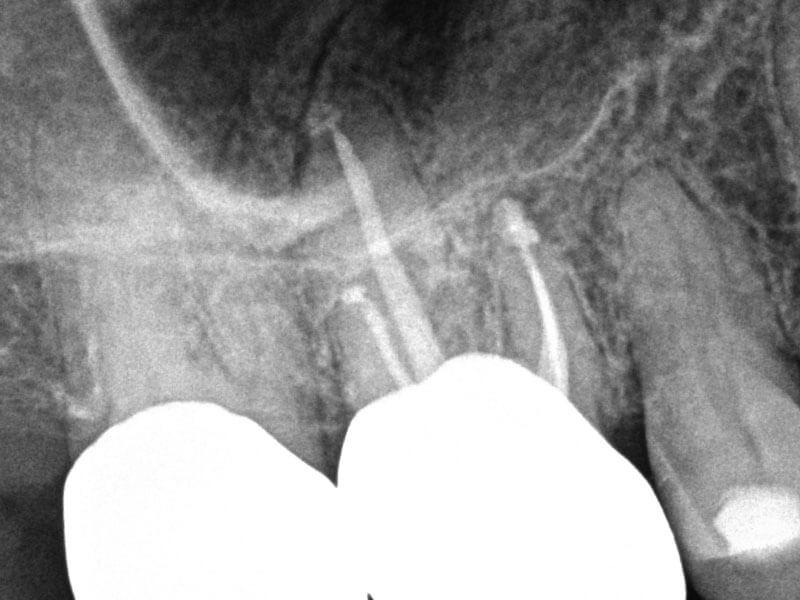

Guarded Pre-Op

Guarded Pre-Op with 3 Months Healing Evidence

Karen S. Potter, DDS

View Case Images